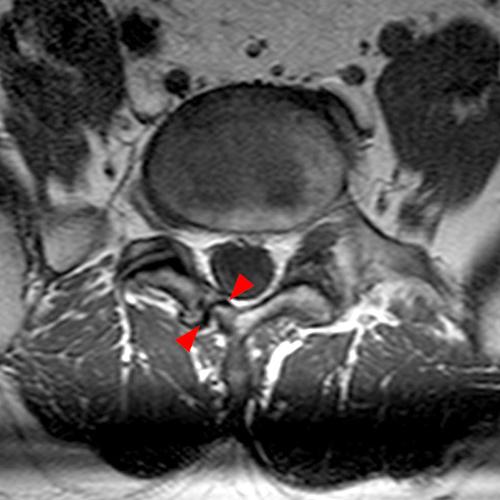

Case 2: T1-weighted (4A) and T2-weighted (4B) axial images show T1 hypointensity and T2 hyperintensity (arrowheads) in the left lamina of L5 adjacent to a small hypointense line (arrows) which traverses the lamina.

Case 2: Acute left-sided laminolysis